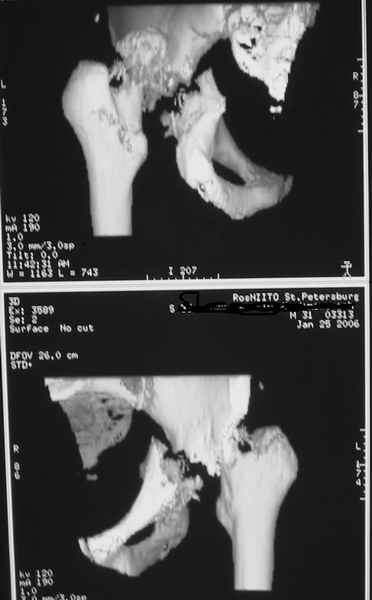

Таз+шейка

Дорогие коллеги, Поступил пациент, 5 месяцев, как сломался.

Поступил для эндопротезирования, но наши корифеи засомневались, не собрать ли сначала таз. Есть ли смысл собирать аппаратом закрыто?